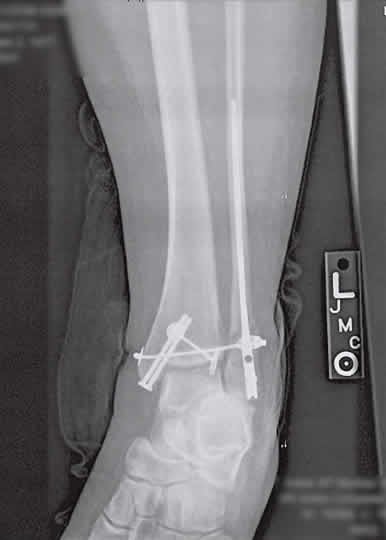

The kind of broken leg that requires Terminator-like rods, cables, screws and pins to fix. Along with six months to a year to recover. And walkers, wheelchairs, shower chairs…grab bars.

So, I was at the hospital, waiting for Star to come out of surgery, and I’m watching the doctors (surgeons) walking in and out of the doors leading to the operating rooms. I notice one doctor walk out with a cordless drill/screwgun. He smiled at me as I must have had one of those what-the-heck-are-you-doing-with-that looks on my face.

Nah… I’m thinking. That’s NOT the drill they are using to put some hardware into my wife’s leg.

Oh yes they did. Well I think they did. It was green and black, maybe a Hitatchi or something.